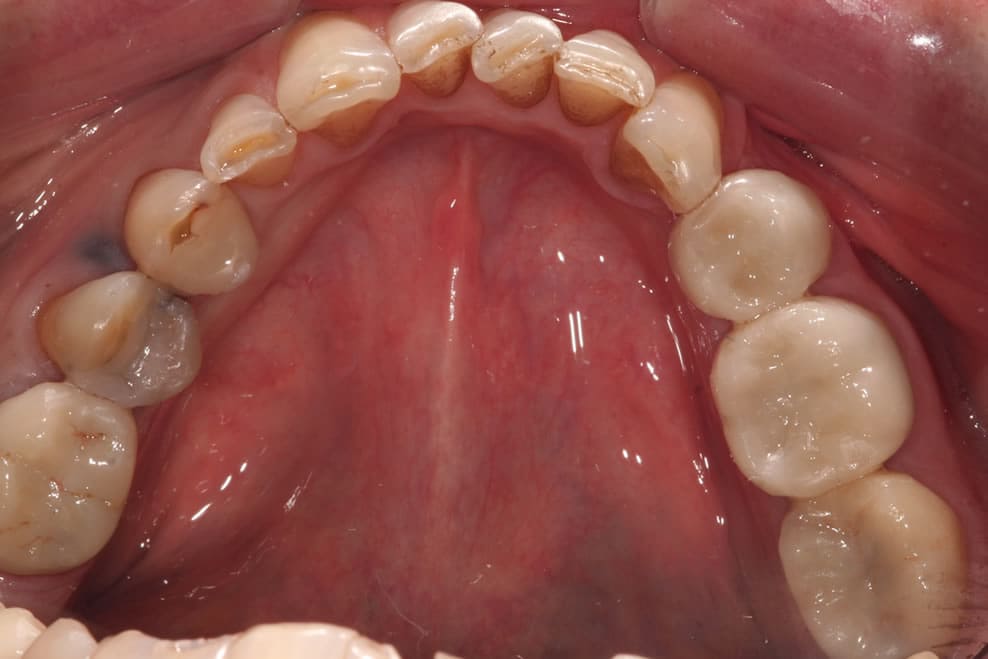

If you have a broken or decayed tooth, a composite filling can be used to restore the tooth to its original shape and colour.

Composite fillings can also be used for cosmetic purposes to restore chipped or uneven front teeth. Many patients also opt to have composite fillings used to replace old, unsightly silver fillings.